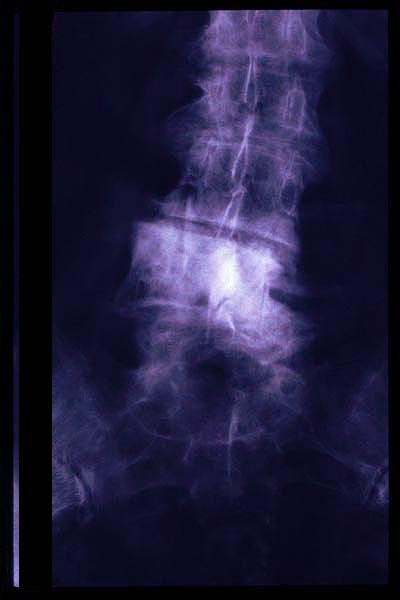

Osteoporosis. Cifosis.